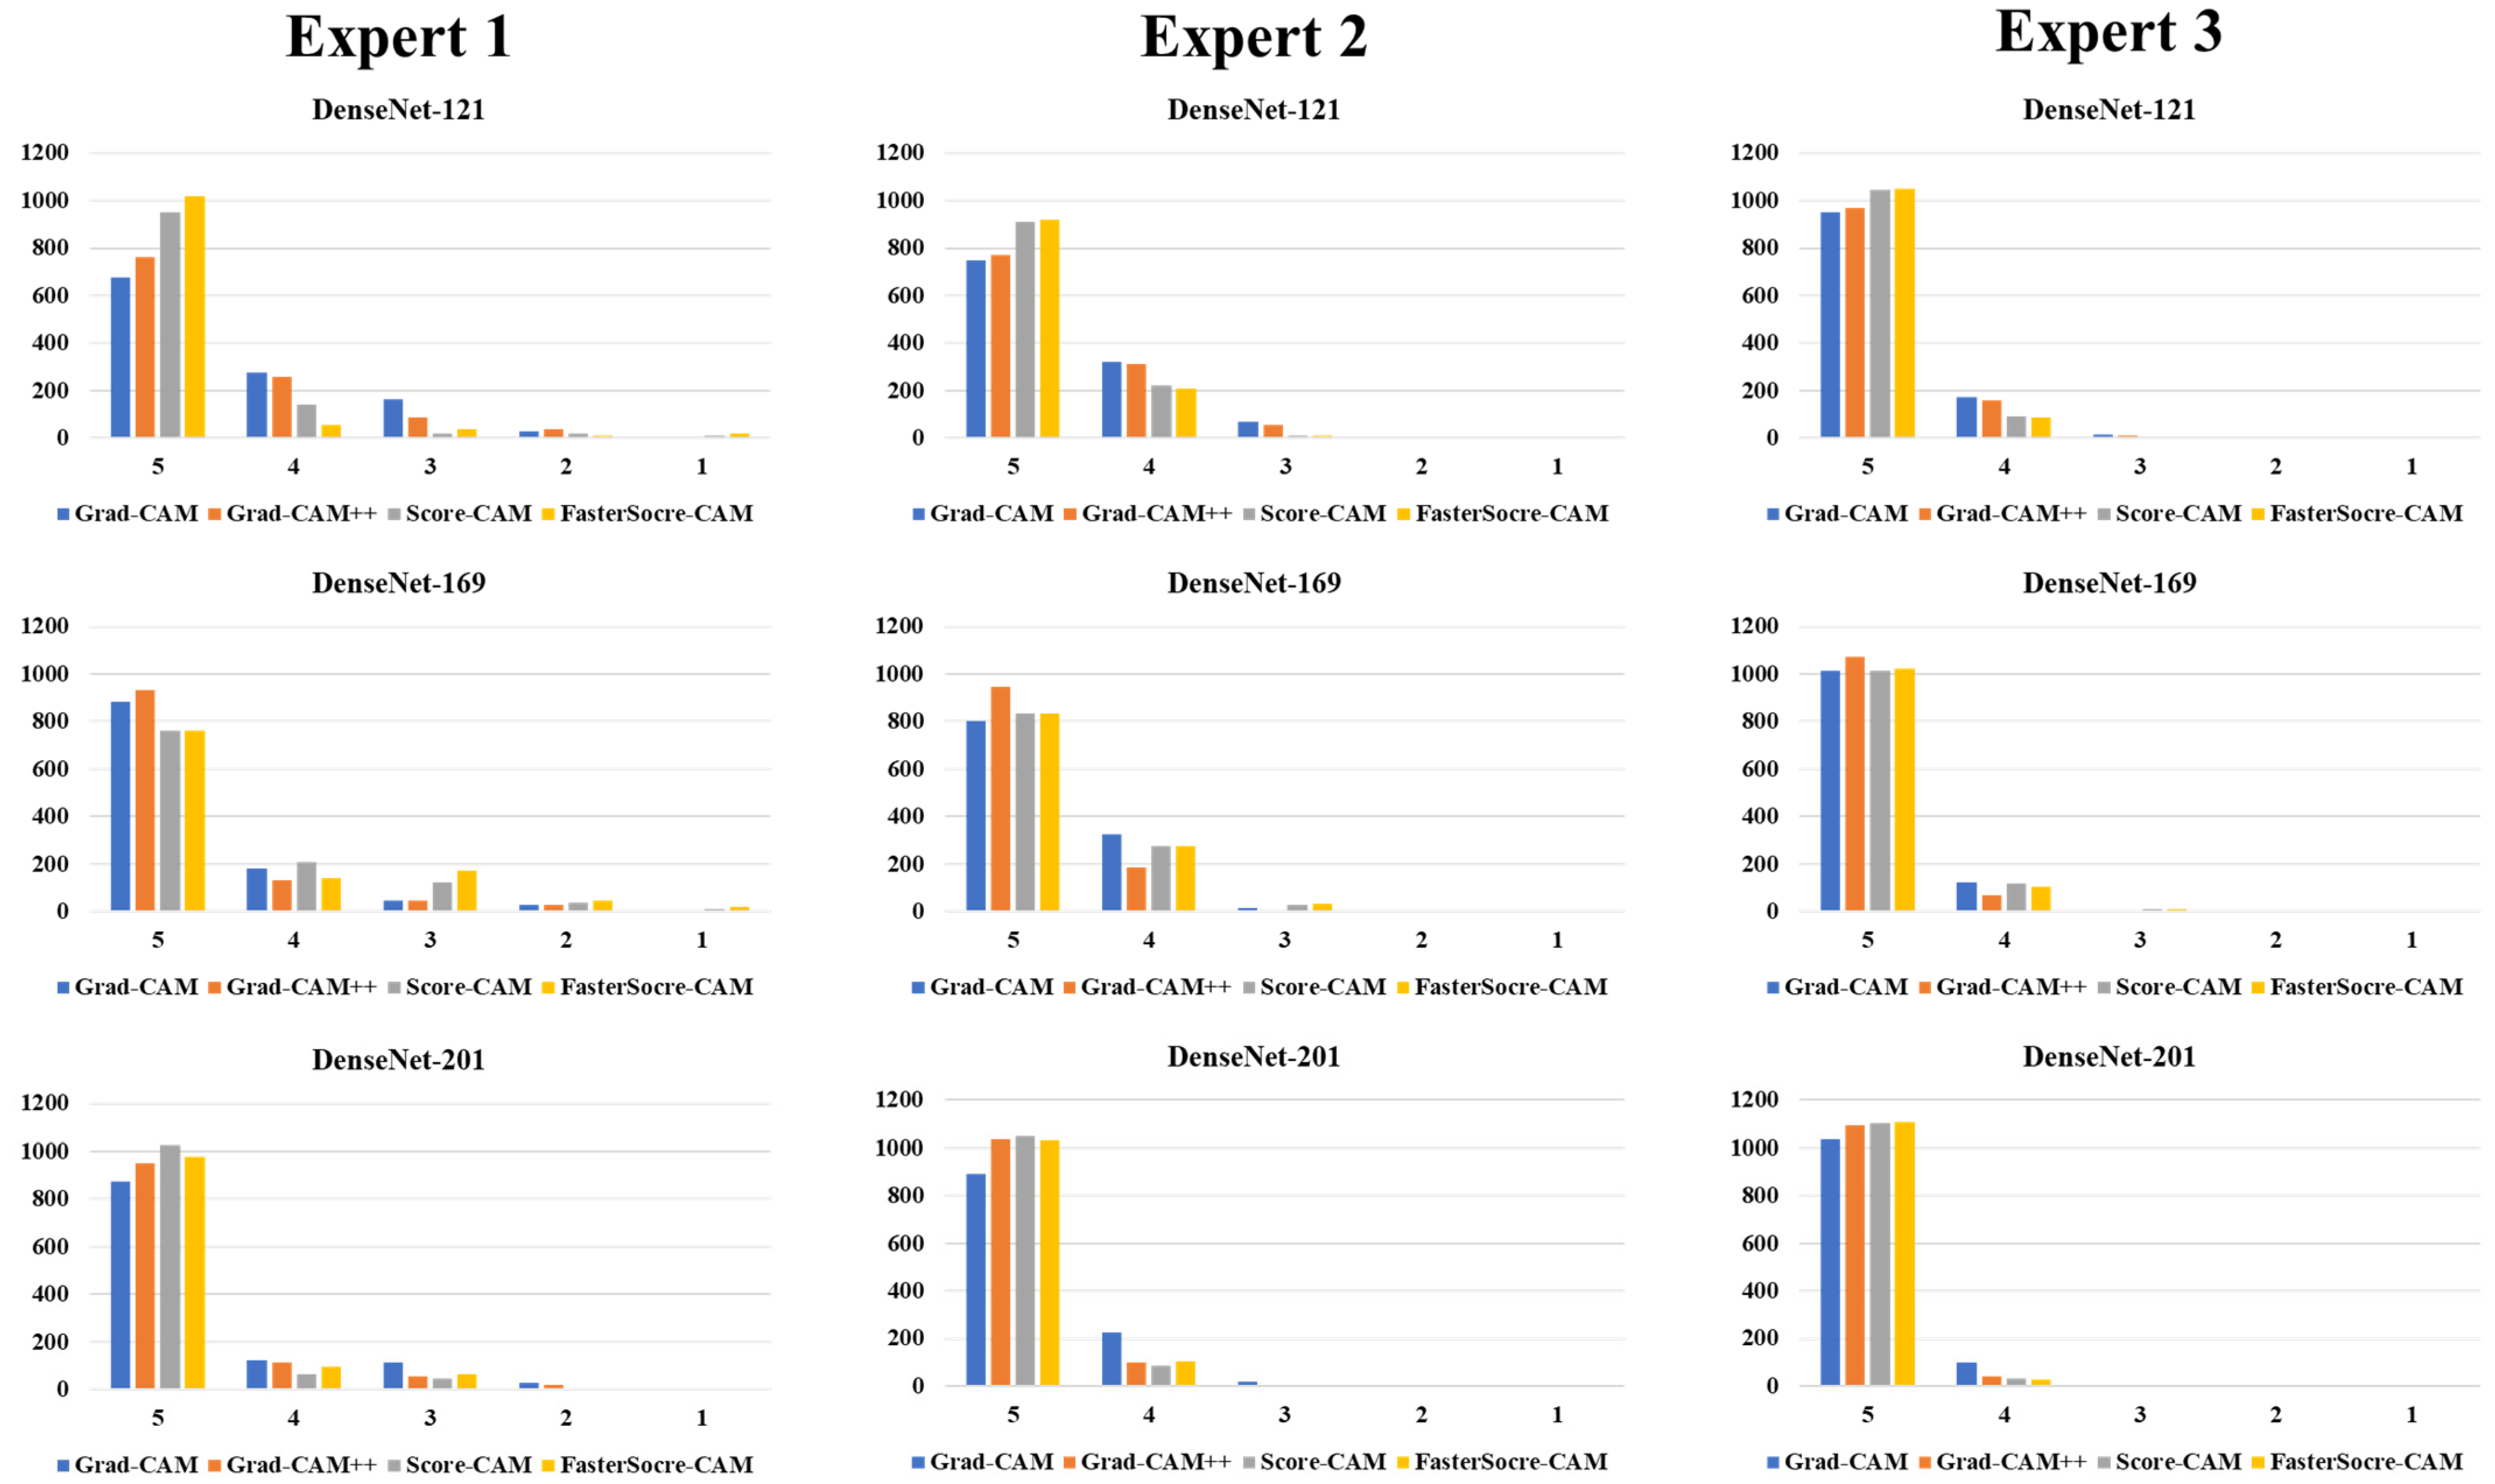

Visual Results Representing Lesion Using the Four CAM Techniques

3.3. Statistical Validation

4.1. Study Findings

4.4. A Special Note on Four CAM Models